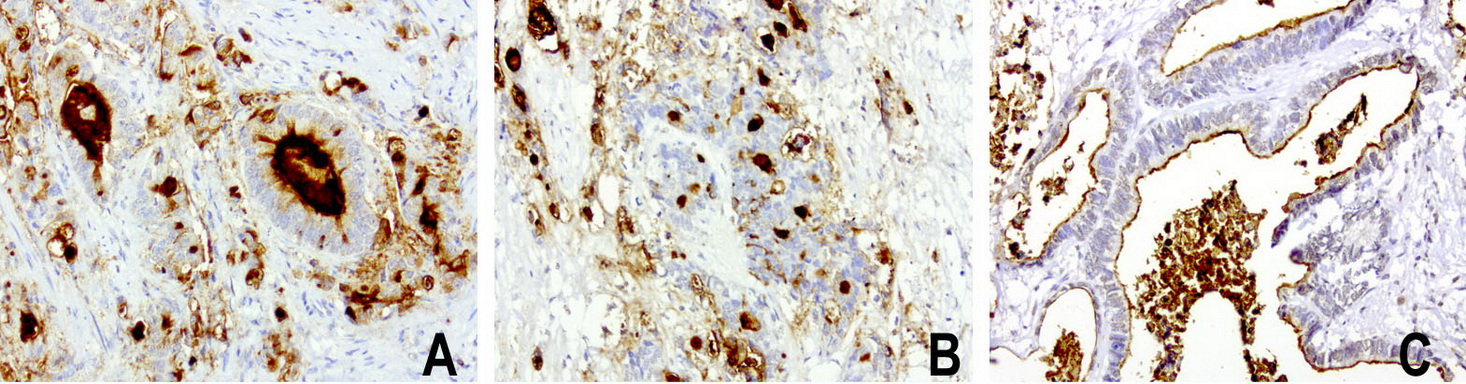

Immunohistochemical staining of paraffin-embedded human colon cancer using anti-MUC1 (EMA) mouse monoclonal antibody at 1:200 dilution of 1mg/mL using Polink2 Broad HRP DAB for detection. BD-PE0664 requires heat-induced epitope retrieval with Accel pH8.7 at 110°C for 3min using pressure chamber/cooker. The image is a composite of 3 tumors which show strong membranous and secreted protein however >75 % tumor cells are negative for cytoplasmic staining.

Immunohistochemical staining of paraffin-embedded human ovarian carcinoma using anti-MUC1 (EMA) mouse monoclonal antibody at 1:200 dilution of 1mg/mL using Polink2 Broad HRP DAB for detection. BD-PE0664 requires heat-induced epitope retrieval with Accel pH8.7 at 110°C for 3min using pressure chamber/cooker. The image is a composite of 3 tumors which show strong membranous and weak cytoplasmic staining in >75 % tumor cells.

Immunohistochemical staining of paraffin-embedded human stomach carcinoma using anti-MUC1 (EMA) mouse monoclonal antibody at 1:200 dilution of1mg/mL using Polink2 Broad HRP DAB for detection. BD-PE0664 requires heat-induced epitope retrieval with Accel pH8.7 at 110°C for 3min using pressure chamber/cooker. The image is a composite of 3 tumors which show strong membranous and cytoplasmic staining in >75 % tumor cells.